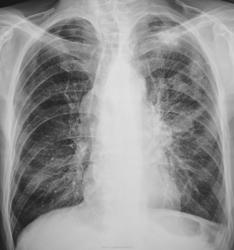

и обсеменением.

Направлен был, как "клиническое излечение".

из нас прав! Здесь  палочки Коха врачам не помощники. Нужны предшествуюшие рентгенограммы.

После этого исследования мокроту пообследовали..., и "балеринок" нашли...

А, помеченные Вами "распадики", на экране профессионального монитора (томограммы) хорошо были видны. Я не стал выставлять все срезы, выставил только оптимальный.

лаборантов. При ничтожных распадах найти МБТ это  - здорово. Молодцы!.

Томограммка у Вас  роскошная!(само качество и исполнение снимка) 5!